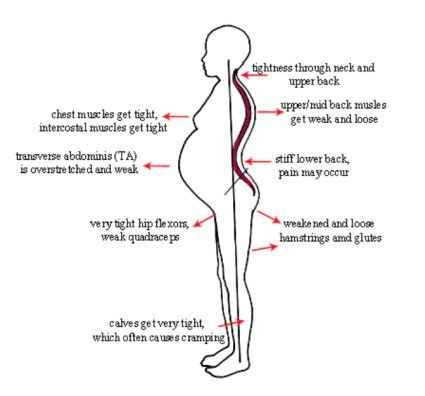

Let’s just cover the bases of pregnancy and birth before we dive into the analysis of women’s rehabilitation. Pregnancy, for perspective here, is when a woman becomes the host of a developing fetus that slowly grows into an actual human-being. This growing human being occupies the limited space inside of her pelvic cavity and torso for nine months. Over this period of time, the host’s major organs get shoved up into the lungs and ribcage, digestion slows down and chronic inflammation spreads into every system of the body while hormones surge to relax and stretch the muscles, tissues and ligaments, the skeletal structure shifts and rotates in order to support the caustic changes to the anterior anatomy (#babybump), and adjust to the increased pressure on all of the nerves and joints throughout the body.

into an actual human-being. This growing human being occupies the limited space inside of her pelvic cavity and torso for nine months. Over this period of time, the host’s major organs get shoved up into the lungs and ribcage, digestion slows down and chronic inflammation spreads into every system of the body while hormones surge to relax and stretch the muscles, tissues and ligaments, the skeletal structure shifts and rotates in order to support the caustic changes to the anterior anatomy (#babybump), and adjust to the increased pressure on all of the nerves and joints throughout the body.

- Pelvic and spinal alignment

- Plumb line Posture

- Body mechanics